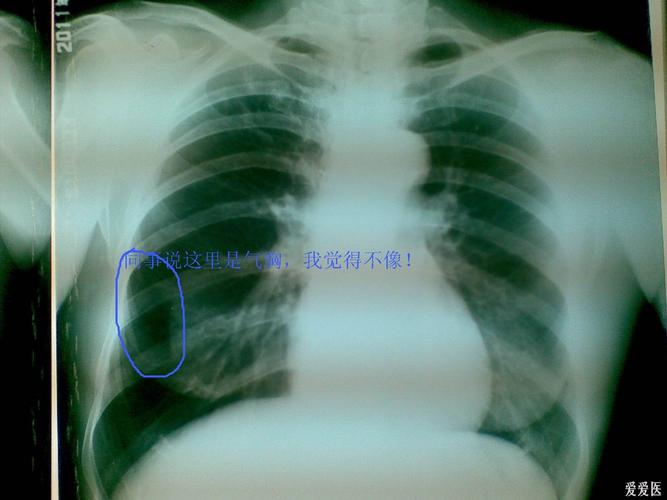

帮看一下胸片,同事报的是气胸,我觉得不像呀!已经做ct

气胸胸片典型图片

气胸x线胸片图解

气胸胸片

气胸的x线表现